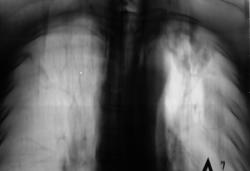

Пациент находится на диспансерном учете в туб. кабинете, по поводу инфильтративного туберкулёза верхней доли левого лёгкого, получает специфическое лечение. Пациент направлен в рентгеновский кабинет для рентгенологического исследования исследования органов грудной полости "в динамике". Проведено стандартное исследование.

Для сравнения приводятся изображения, произведенные чуть больше года тому.